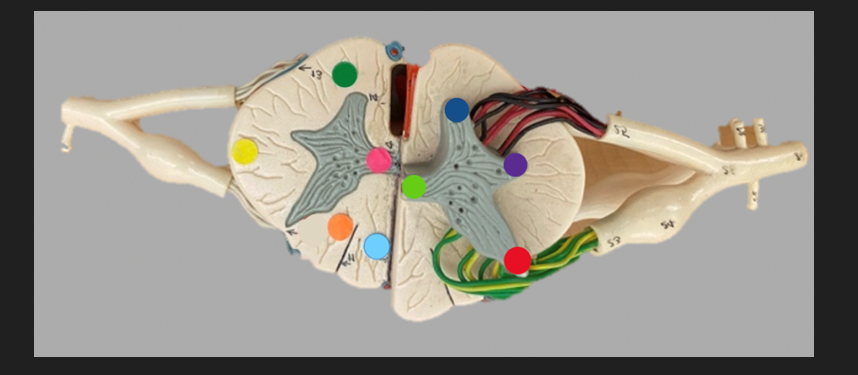

green dot

spinal nerve

orange dot

ventral root

pink dot

dorsal root

blue dot

dorsal root ganglion

red dot

dorsal ramus

yellow dot

ventral ramus

purple dot

anterior median fissure

red dot

posterior (dorsal) horn

purple dot

lateral horn

dark blue dot

anterior (ventral) horn

orange dot

dorsal column

yellow dot

lateral column

dark green

anterior column

line green and pink doit

gray commissure

light blue dot

posterior median sulcus